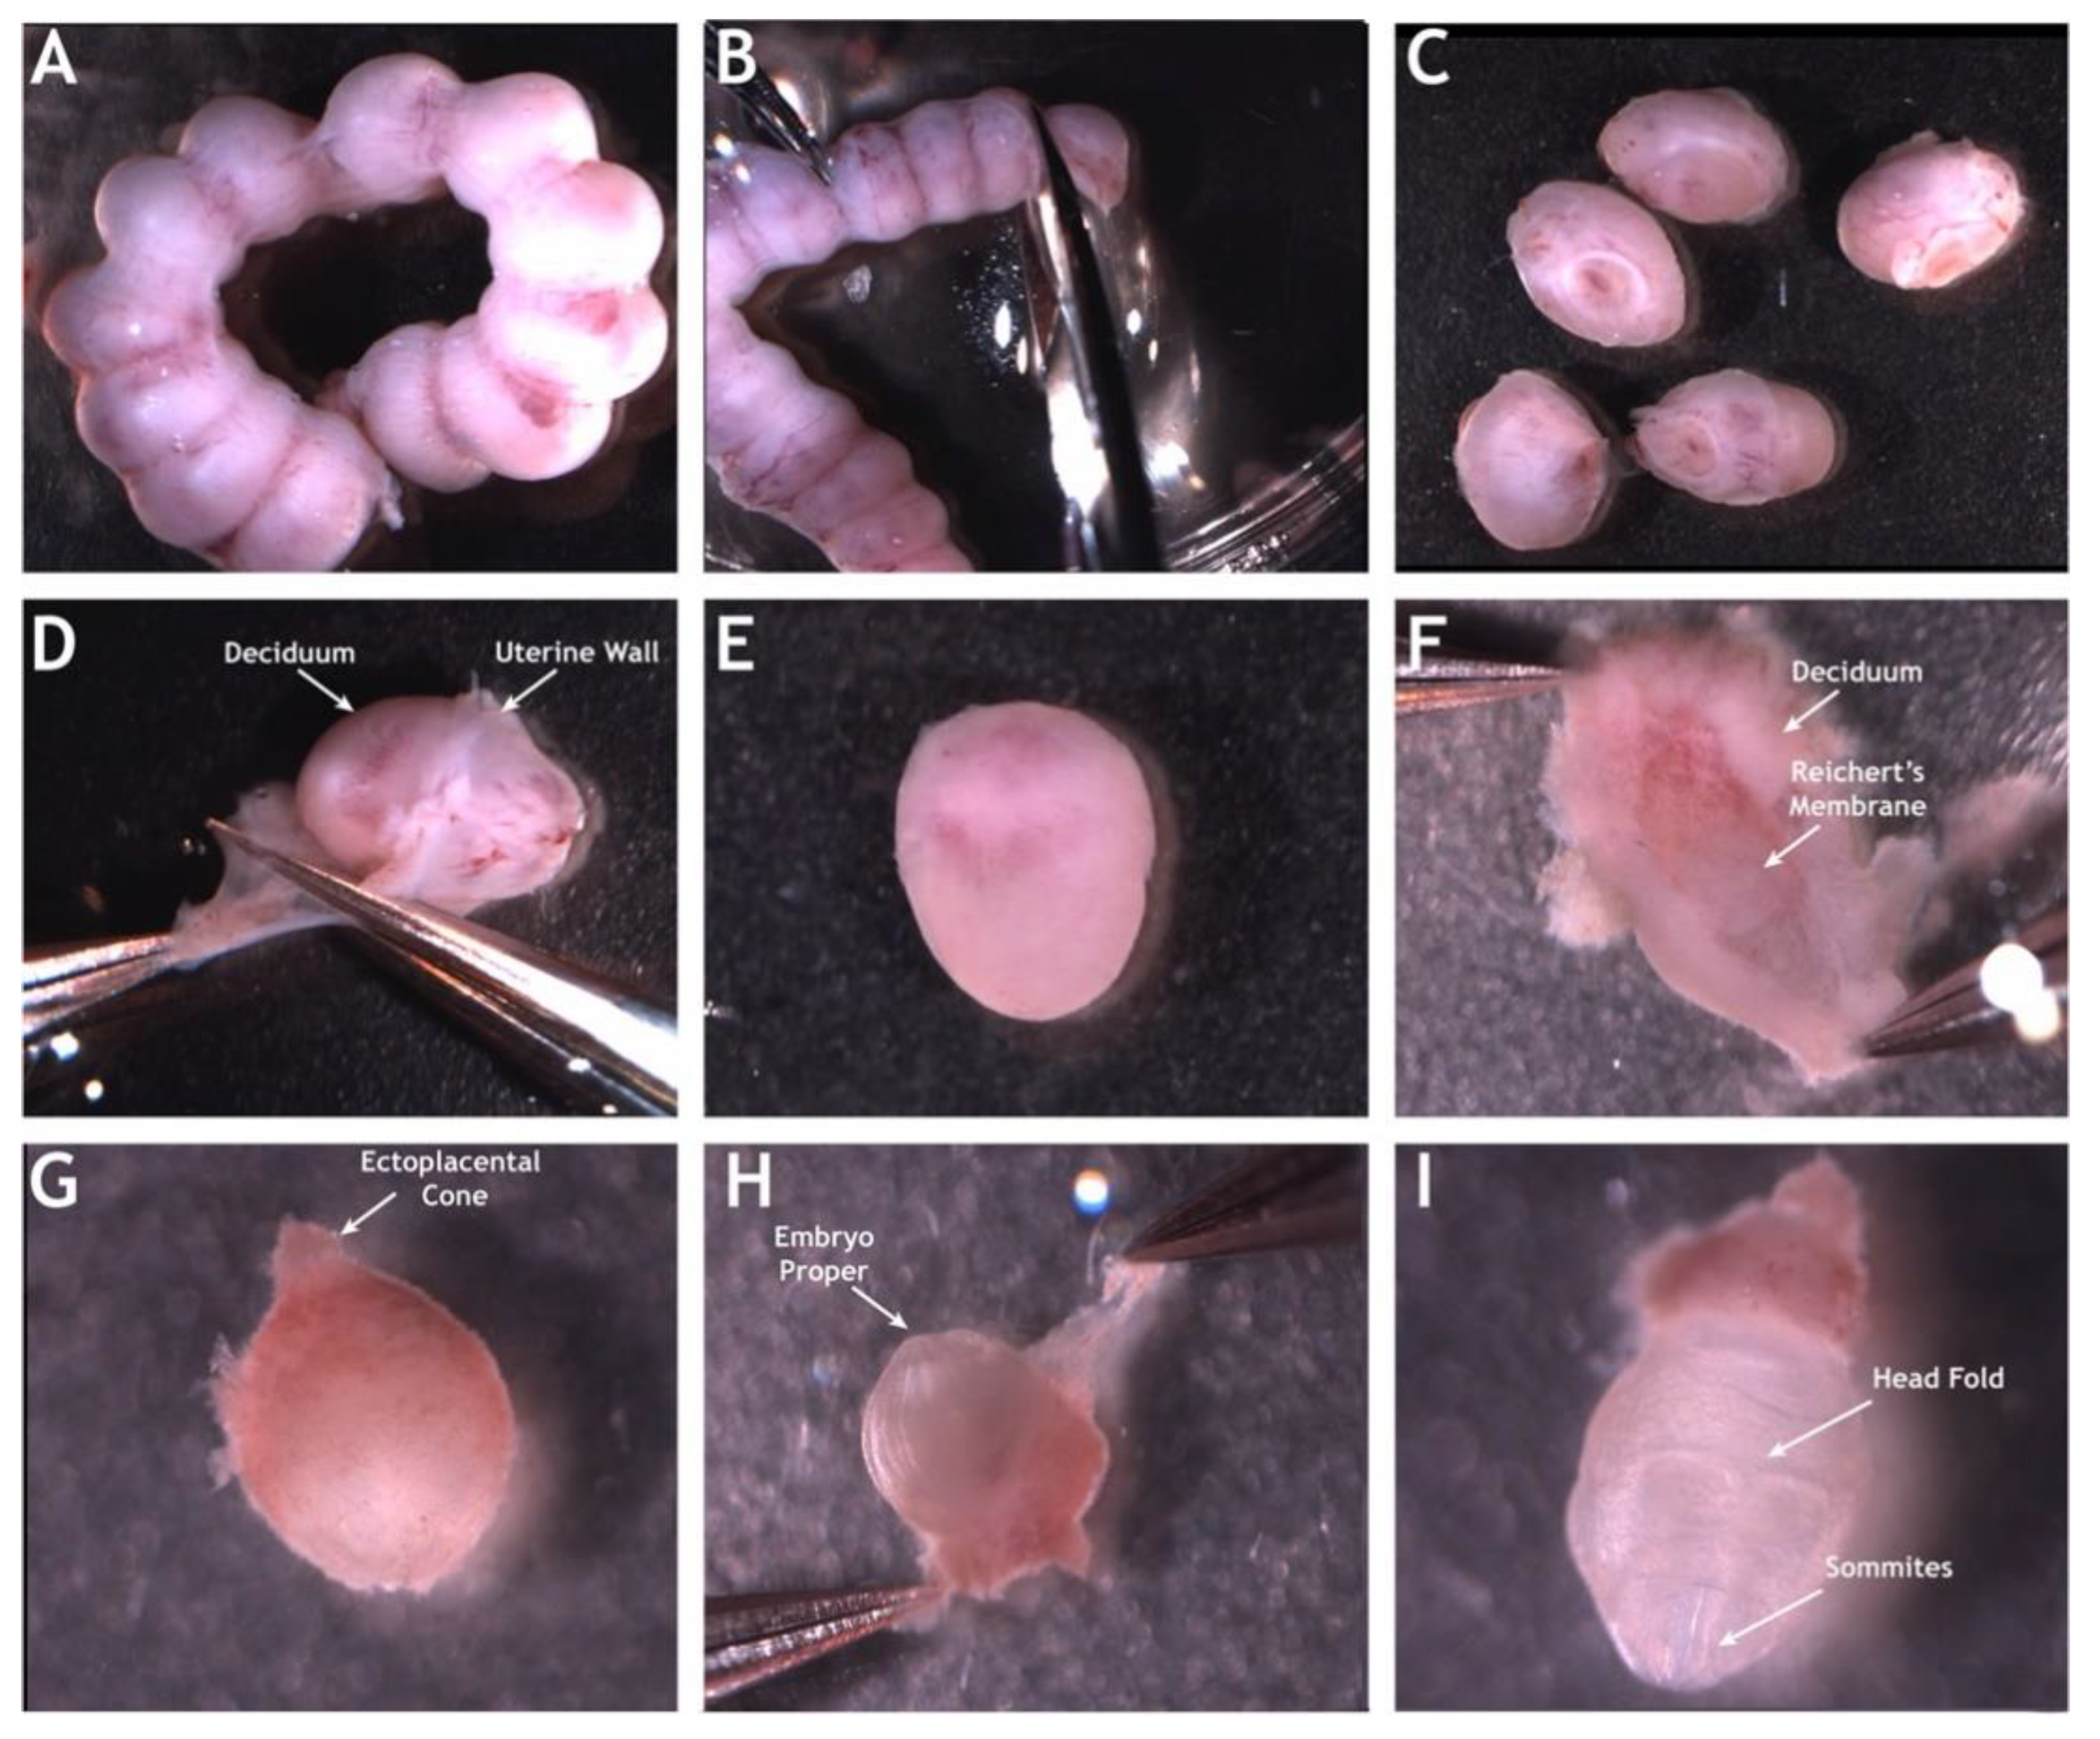

2. Mouse Embryonic Imaging in Static Culture

- Lopez, R.A.L.; Larina, I.V. Dynamic Imaging of Mouse Embryos and Cardiodynamics in Static Culture. Methods Mol. Biol. 2018, 1752, 41. [Google Scholar]